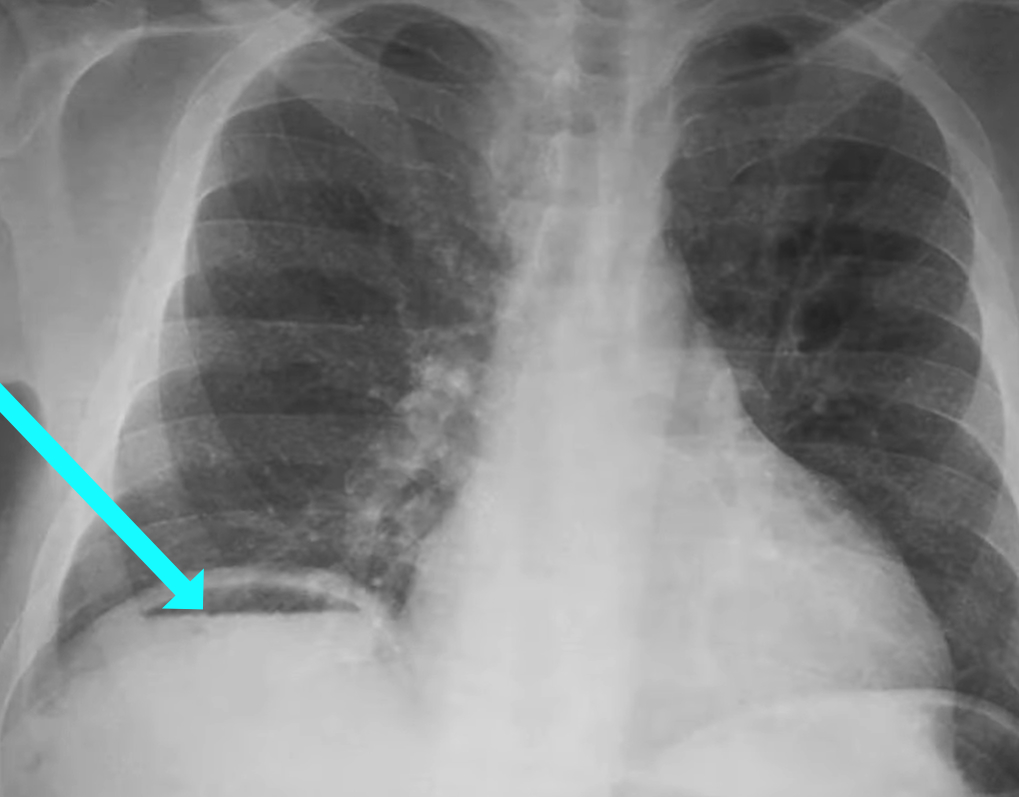

To what structure is the arrow pointing?

C) Air fluid level